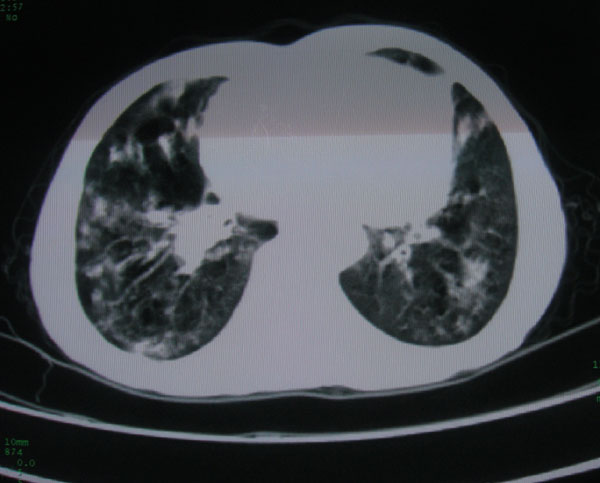

标题: CT15046:F59Y,咳嗽间断咳血丝痰就诊. [打印本页]

标题: CT15046:F59Y,咳嗽间断咳血丝痰就诊.

咳嗽\间断咳血丝痰就诊.

考虑支气管扩张并感染

1\\慢支并感染

2\\浸润型肺结核

本例应该是“慢性疾病并发多种合并症”即:慢支并感染并支气管扩张征!结合病灶分布 形态分析,不除外合并“继发性肺结核”!

慢性支气管炎伴全小型肺气肿、支气管扩张、感染、间质纤维化。

多考虑支气管扩张并感染,双下肺继发性肺结核不除外